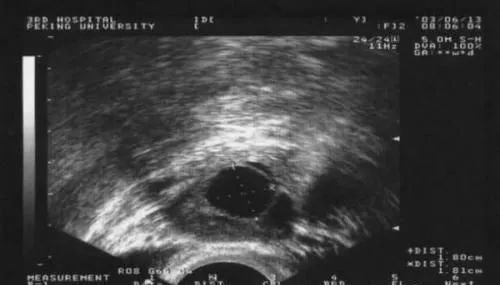

5.B超检测:一般在月经的第10-12天开始监测,若需要促排卵的患者一般在月经第5天开始促排卵,第10天复查B超。当卵泡生长到18-20mm时卵泡成熟,即将排卵;卵泡消失或体积明显缩小,边缘皱缩,出现锯齿状,后穹窿出现积液是说明卵泡已破裂,排出卵泡液。

总之,最直接的监测方式就是阴道B超检测排卵。